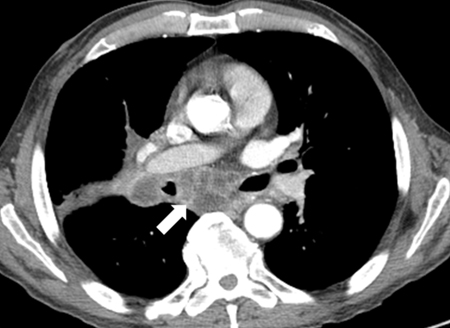

Computed tomography (CT)

CT with intravenous contrast enhancement provides information concerning the vascularisation of the mass and its relationship to adjacent structures.[49]​ It can determine the content (calcium, fat, or necrotic tissue) and characteristics (cystic or solid) of the mass. CT scan is an essential test and is indicated in virtually all cases to evaluate a mediastinal mass.[Figure caption and citation for the preceding image starts]: CT image of large thymic carcinoma (white arrow) with sternal invasion (yellow arrow)From the collections of Dr Mario Gasparri and Dr Nicholas Choong [Citation ends].com.bmj.content.model.assessment.Caption@7ae6cbfb[Figure caption and citation for the preceding image starts]: CT image of pericardial cystFrom the collections of Dr Mario Gasparri and Dr Nicholas Choong [Citation ends].com.bmj.content.model.assessment.Caption@456940f5[Figure caption and citation for the preceding image starts]: Necrotic mediastinal lymphadenopathyFrom the collections of Dr Mario Gasparri and Dr Nicholas Choong [Citation ends].com.bmj.content.model.assessment.Caption@5e726e38​​​